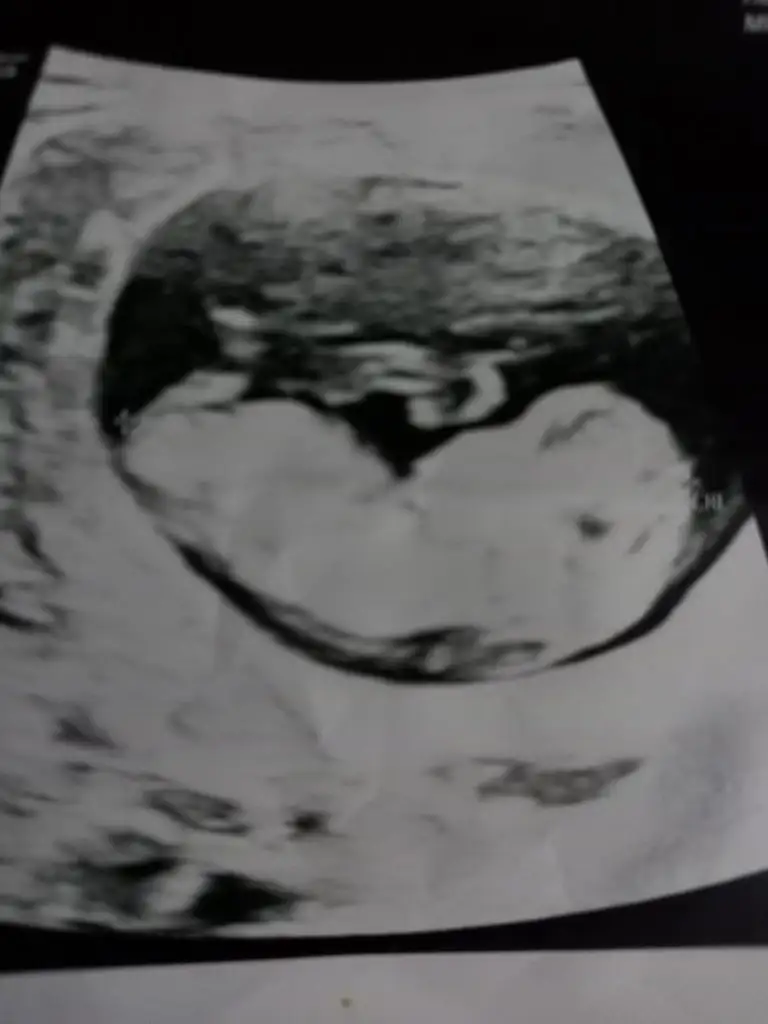

Oyyyy kıyamam mucize gerçektenİçimizi ferah tutalım her şey güzel ilerleyecek minik kuzu büyüyor

Yalnız dış gebelik falan olup olmadığına daha erken bakmaları gerekmez mi kafamda deli sorular

Dış gebelik ağrı ve kanamaya sebebiyet verdiği için acile vs gidince belli oluyordur herhalde bilmiyorum aslında benim de en çok merak ettiğim konulardan biri dış gebeliği nasıl teşhis edecekler 13 hafta geç değil mi vs..